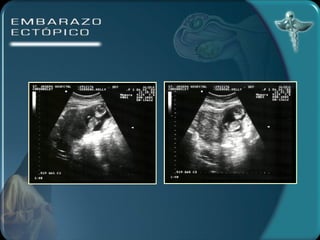

DIAGNÓSTICO Por imagen Ecografía transvaginal útero vacío 100% tumor parauterino 85 % embrión 55% Anillo tubárico Líquido en el fondo del saco

DIAGNÓSTICO Por imagenEcografía transvaginal útero vacío 100% tumor parauterino 85 % embrión 55% Anillo tubárico Líquido en el fondo del saco

• #23 DIAGNÓSTICO )LABORATORIO: la hemoglobina y el hematocrito pueden ser de utilidad para el seguimiento de la paciente. Estos valores pueden no alterarse precozmente ante una hemorragia.La leucocitosis puede estar presente en el 50% de los casos mientras que el otro 50% permanece con valores normales.La gonadotrofina coriónica humana puede investigarse en suero o en orina. Las pruebas urinarias son de poca sensibilidad en esta patología. Con la prueba de ß HCG en suero se puede detectar todo tipo de embarazos. Los niveles de la ßHCG se correlacionan con la edad gestacional. Durante las primeras 6 semanas de gestación los niveles séricos se incrementan en forma exponencial ( la duplicación del valor de la ßHCG es constante), después de las 6 semanas (nivel de la ßHCG de 6000 a 10000 mUI/ml) el ascenso se hace más lento y menos constante. Cundo los niveles de ßHCG son bajos (por debajo de 1000 mUI/ml) el valor absoluto es menos útil para diferenciar un embarazo normal de uno extrauterino. 2) ECOGRAFÍA TRANSABDOMINAL A) ÚTERO VACÍO B) MASA ANEXIAL C) LÍQUIDO EN EL FONDO DE SACO Con este método no es posible diagnosticar embarazos pequeños de 5 a 7 semanas. 3) ECOGRAFÍA TRANSVAGINAL A) ANILLO TUBÁRICO: un anillo ecogénico alrededor de un centro hipoecogénico como estructura encontrada fuera del útero. B) LÍQUIDO EN EL FONDO DE SACO Este método permite un diagnóstico precoz del embarazo ectópico 4) CULDOCENTESIS: se realiza cuando se detecta una colección líquida en el saco de Douglas. 5) LAPAROSCOPÍA: permite establecer el diagnóstico definitivo.